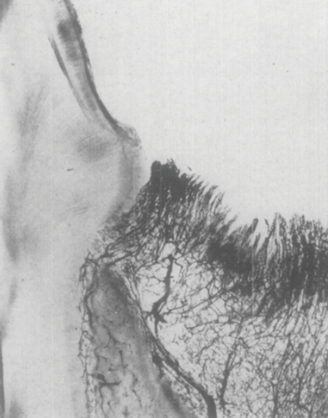

It has been established that the critical vascular supply to the periodontium and supportive alveolar bone is threefold22,23: (1) within the periosteum of the alveolar bone (Figure 1); (2) within the cancellous portion of the alveolar bone proper (Figure 1 and Figure 2); and (3) a vascular plexus within the PDL itself (Figure 2 and Figure 3). This further clarifies the fact that not only does the periodontal functional unit have components that are interdependent to each other, but critical vascular supply to the alveolar bone is composed of three unique units.

Disruption or loss of any one or two of these essential vascular entities would be enough to tip the balance of buccal bone health and survival into atrophy and loss. It is the intraseptal artery contained within the alveolar bone that provides blood supply to the vascular plexus of the PDL. After penetrating the cribriform plate of the socket walls, these vessels create a lattice-like anastomosis encompassing the root structure in a similar manner to a basket.24 This appreciation for the presence of a critical blood supply has also been reviewed as reported observations related to the presence or absence of interdental papillae as a function of the linear distance to the apex of the corresponding interseptal bone.25-27 The authors discussed the critical nature of the blood supply within the PDL to the survival of the interseptal bone, also noting that this blood supply influenced the surrounding soft tissues and their long-term contours.

Fig 2. Photomicrographs illustrating vascular supply to the periodontium and supportive alveolar bone. Fig 1 shows the presence of a vascular network within the periosteum on the buccal aspect of the alveolar bone and within the cancellous aspect of the alveolar bone. Fig 2 demonstrates the vascular blood supply found within the PDL space adjacent to a tooth that has been sectioned in a buccolingual dimension. The blood supply to the cancellous bone and periosteum is also demonstrated in this section. (Images republished with permission of C.V. Mosby Co., from Keller GJ, Cohen DW. Oral Surg Oral Med Oral Pathol. 1955;8(5):539-542. Permission conveyed through Copyright Clearance Center, Inc.)

Figure 2